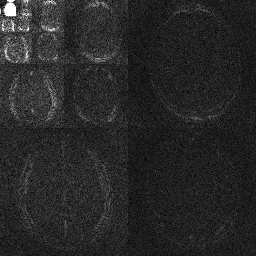

Magnetic Resonance Imaging (MRI) has excellent soft tissue contrast but is hindered by an inherently slow data acquisition process. Compressed sensing, which reconstructs sparse signals from incoherently sampled data, has been widely applied to accelerate MRI acquisitions. Compressed sensing MRI requires one or more model parameters to be tuned, which is usually done by hand, giving sub-optimal tuning in general. To address this issue, we build on previous work by the authors on the single-coil Variable Density Approximate Message Passing (VDAMP) algorithm, extending the framework to multiple receiver coils to propose the Parallel VDAMP (P-VDAMP) algorithm. For Bernoulli random variable density sampling, P-VDAMP obeys a "state evolution", where the intermediate per-iteration image estimate is distributed according to the ground truth corrupted by a zero-mean Gaussian vector with approximately known covariance. To our knowledge, P-VDAMP is the first algorithm for multi-coil MRI data that obeys a state evolution with accurately tracked parameters. We leverage state evolution to automatically tune sparse parameters on-the-fly with Stein's Unbiased Risk Estimate (SURE). P-VDAMP is evaluated on brain, knee and angiogram datasets and compared with four variants of the Fast Iterative Shrinkage-Thresholding algorithm (FISTA), including two tuning-free variants from the literature. The proposed method is found to have a similar reconstruction quality and time to convergence as FISTA with an optimally tuned sparse weighting and offers substantial robustness and reconstruction quality improvements over competing tuning-free methods.